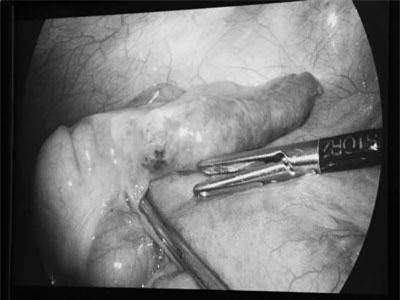

Thị trấn Villa Las Estrellas ở Nam Cực là một nơi khá đặc biệt khi tất cả những cư dân muốn tới đây định cư đều phải chấp nhận cắt bỏ ruột thừa để đảm bảo tính mạng.

Một thị trấn ở Nam Cực yêu cầu tất cả những người dân trước khi đến đây sinh sống đều phải cắt bỏ ruột thừa.

Để tránh bị viêm ruột thừa và có thể vỡ bất cứ lúc nào, bác sĩ trẻ 27 tuổi thuộc đoàn thám hiểm của Liên Xô tại Nam Cực đã tự mổ ruột thừa và cứu sống mình.